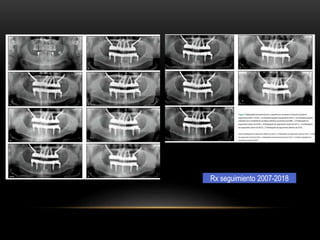

Rx seguimiento 2007-2018

Materiales y métodos: 102px pacientes rehabilitados mediante cirugía de implante cigomático 206 implantes 2006 a 2017 en clínica privada se colocaron 1,2, o 3 implantes cigomáticos en combinación con implantes convencionales. o se colocaron 4 implantes cigomáticos solos Abordaje quirúrgico guiado por anatomía y fueron inmediatamente cargados con prótesis provisionales atornilladas hasta el final de la fase de osteointegración.